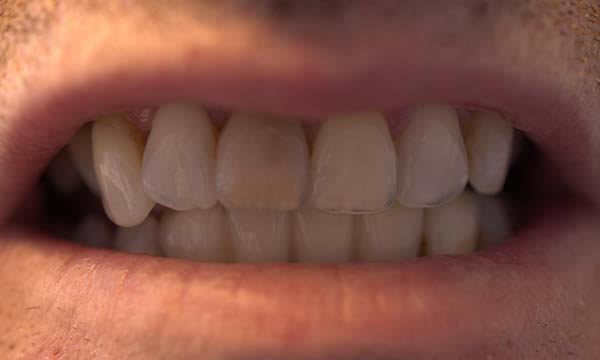

This gentleman had lost his heavily restored UL4 and decided to close the space with an implant retained crown. The thin buck-palatal width required careful placement to avoid fenestration bucally. A tooth bourn position guide was used to place the implant predictably and within the aesthetic envelope. The implant was restored after three months of osseointegration with a bonded crown.